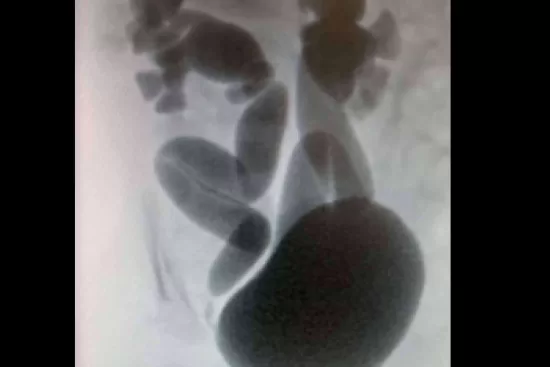

El diagnóstico del reflujo vesicoureteral en recién nacidos se realiza mediante pruebas especializadas, siendo la cistouretrografía miccional (VCUG) una de las más comunes. Esta prueba permite observar el reflujo de la orina y clasificar el grado de severidad, que va desde el I hasta el V. El Dr. Daniel Cabezalí señala que esta clasificación es fundamental, ya que influye directamente en la elección del tratamiento, que puede variar desde la vigilancia activa hasta la cirugía en los casos más graves.

El VCUG se recomienda especialmente si el recién nacido ha sufrido infecciones urinarias recurrentes o si se ha detectado hidronefrosis, una dilatación de los riñones durante las ecografías prenatales. El Dr. Cabezalí subraya la importancia de un diagnóstico preciso y temprano para evitar complicaciones mayores, como infecciones renales que pueden llevar a la cicatrización del tejido renal y, en casos extremos, a una disminución de la función renal.